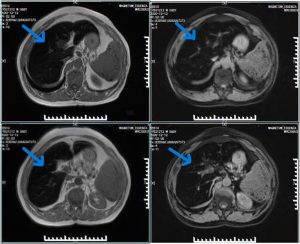

- MRI liver: Diffuse low T1/T2 signal intensity consistent with iron overload (“black liver”)

- MRI (Magnetic Resonance Imaging): Imaging technique; in hemochromatosis shows “black liver” due to iron deposition